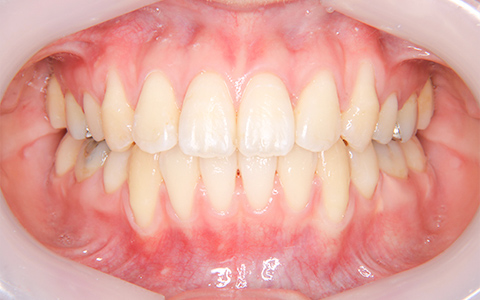

治療前

治療後

施術内容 上の2番目の歯が内側にあることがお悩みでご来院(33歳)。前歯部の叢生・交叉咬合に対するマウスピース型矯正装置(インビザライン)による非抜歯治療

治療期間 1年1ヶ月(通院7回)

費用 880,000円

リスク・副作用 歯が動く痛み、歯髄壊死、歯根吸収、歯肉退縮、リテーナーを使用しないことによる後戻り